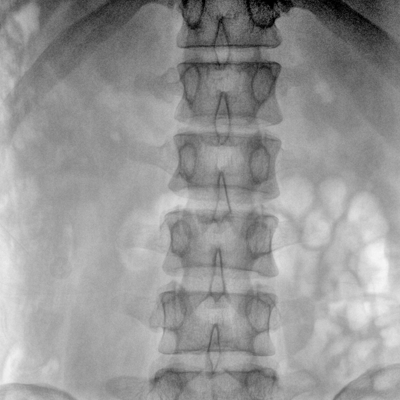

Clinical picture

臨床圖片